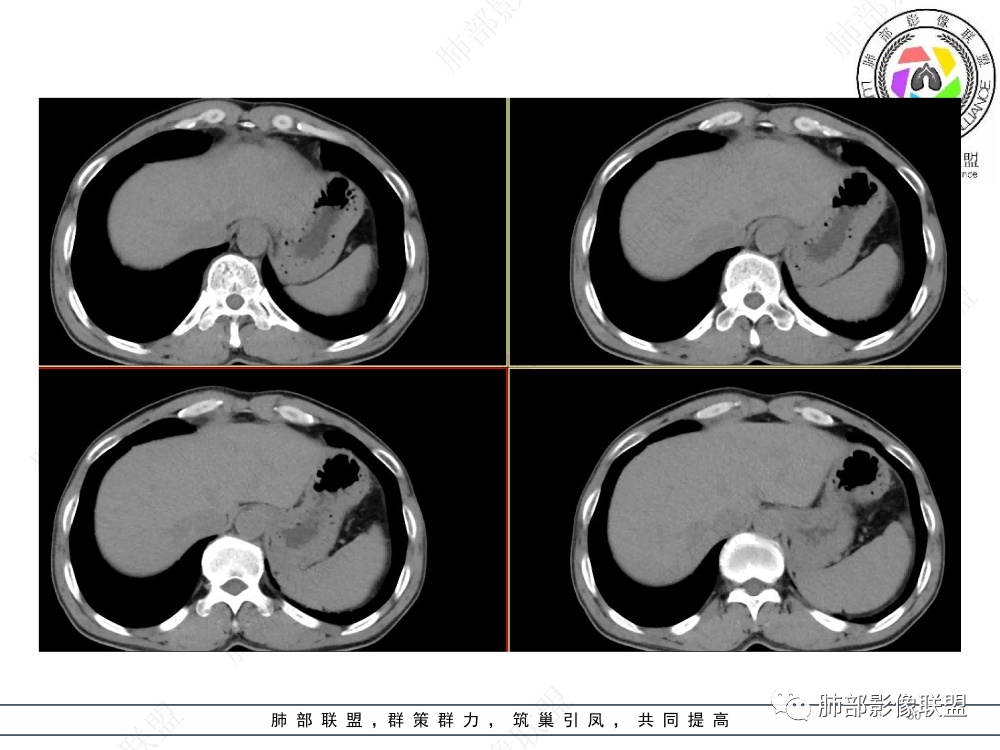

2.影像表现:前上纵隔较大肿块,密度不均,形态不规则,边界不清,有结节样突起,脂肪间隙显示不清。病灶侵犯左无名静脉及上腔静脉,其中左无名静脉闭塞(胸背部侧支循环明显,亦表明回流受阻)。增强后轻中度不均强化。坏死边界欠清晰。可见心包积液,提示心包受侵犯。右侧上叶及纵隔胸膜下结节影,疑胸膜肺转移可能。胸骨柄后缘皮质不完整,疑骨质破坏(未提供骨窗及矢状位图像)。左锁骨上可见肿大淋巴结。